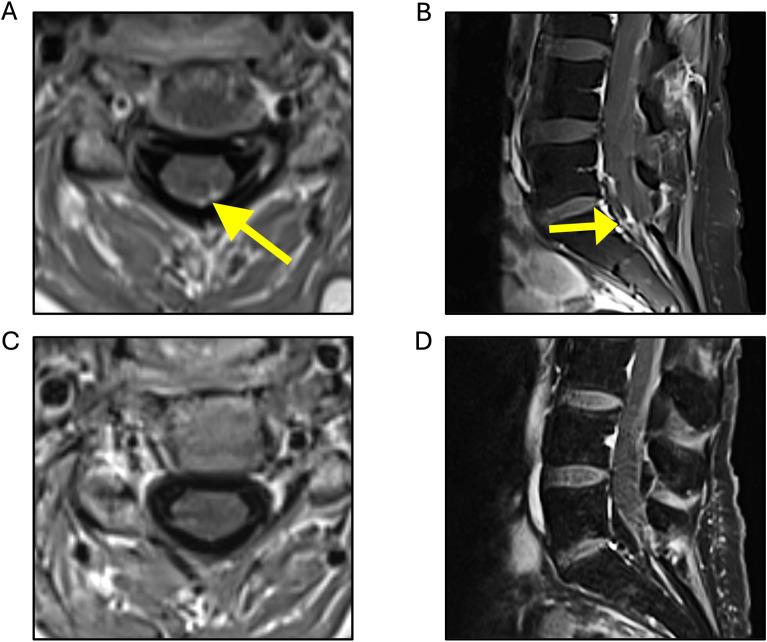

Leptomeningeal carcinomatosis (LC) is a severe complication of metastatic breast cancer (mBC), with rising incidence. The prognosis for patients with LC has been poor, with a median overall survival of approximately four months. However, recent therapeutic advances, in particular the introduction of trastuzumab deruxtecan have dramatically changed the landscape of CNS metastases and improved outcomes. Here, we present the case of a 42-year-old woman with recurrent HER2+ breast cancer who developed extensive LC after multiple lines of treatment. Despite progressive disease, the patient exhibited a sustained response to trastuzumab deruxtecan, a novel antibody-drug conjugate (ADC), for 15 months, which was further extended by adding tucatinib. This case underscores the potential of ADCs, like trastuzumab deruxtecan, in controlling both brain metastases and leptomeningeal disease, offering hope for prolonged survival in patients with aggressive HER2+ mBC. Additionally, we highlight the evolving role of clinical trials, molecular profiling, and interdisciplinary care in managing this challenging condition. Ongoing trials continue to investigate new therapeutic options for HER2+ mBC with CNS involvement, promising to further improve outcomes and quality of life for patients facing this devastating disease.